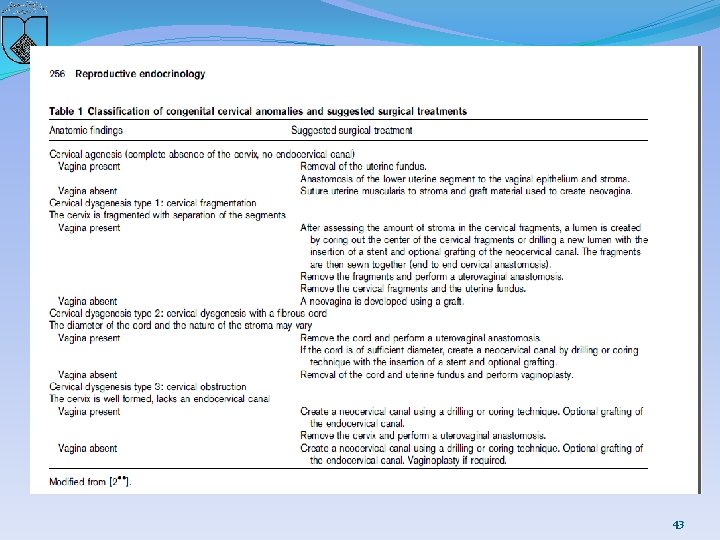

�second type, cervical dysgenesis (1) Cervical body consisting of a fibrous band of variable �length and diameter (endocervical glands may be �noted on pathologic examination; (2) Intact cervical body with obstruction of the cervical �os (cervical ostium; the cervix is usually well formed, �but a portion of the endocervical lumen is obliterated; (3) Stricture of the midportion of the cervix (which is �hypoplastic with a bulbous tip and no identifiable �cervical lumen; (4) Fragmentation of the cervix (with portions that can �be palpated below the fundus and that are not connected �to the lower uterine segment 32

�Historically, the preferred treatment was hysterectomy, given this condition was not considered compatible with future fertility �less aggressive surgical procedures : �uses molds and both skin and "mucosal" grafts to create an upper vagina and cervical endocervical tract to allow menstruation and potentially enable spontaneous conception and successful pregnancy �disadvantages of this approach: risks of recurrent obstruction and ascending infection, which can lead to sepsis and death 34

�A treatment algorithm �clinicians should select a surgical procedure carefully and be certain of the diagnosis (eg, differentiate between a high transverse vaginal septum and cervical agenesis) �A safe, successful surgical procedure is more likely when there is normal cervical tissue that just lacks a patent cervical canal than when there is significant cervical agenesis. 35

recommended approach �The first step : defining the anatomy prior to performing any reconstructive procedure �cervix is a thin cord or the uterine cavity is hypoplastic �or absent, the uterus and cervical remnants are removed �If a reconstructive procedure is performed, epithelialization with a suitable graft of neocervical canal is recommended 41

uterovaginal anastomosis �complete dissection of the rectouterine and vesicouterine space to expose the vagina or neovaginal canal, �allowing circumferential anastomosis of the vagina and stroma to the lower uterine segment. The uterus is pulled down and sutured to the vagina or vestibular mucosa A stent (16 French Foleycatheter) is placed with or without a mold, depending on surgeon preference or the need to graft the newly createdneovagina. �The patient is given a broad-spectrum antibiotic for 15 days. 42

Key points � Hysterectomy is recommended for the patients with complete cervical agenesis. � High uterovaginal graft, at the line of the endometrium in the lower uterine segment, may produce a more successful uterovaginal anastomosis. There is a high risk of stenosis and fibrosis at the anastomosis site. � Cervicovaginal anastomosis may be accomplished in the patients with an endocervical canal. Cervicovaginal anastomosis and cervical grafting may be required. � When necessary, the surgeon should be prepared to perform a vaginoplasty, whether or not the uterus is preserved. � The anatomical findings in the cervix and patient preferences must be used for a comprehensive treatment strategy to afford the most successful outcome. � Complications following uterovaginal anastomosis are not insignificant and include endometritis, pelvic inflammatory disease, persistent pelvic pain, bowel and bladder injury, re-obstruction and stenosis requiring reoperation and death. 44